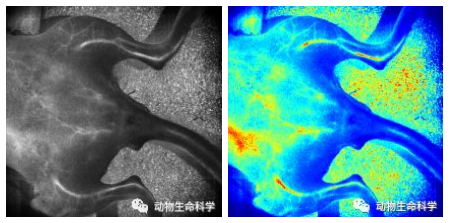

超高2K分辨率(2048 × 2048)

带你清晰观察肠系膜第五分支血管

2-肠系膜第五分支血管.jpg

肠系膜